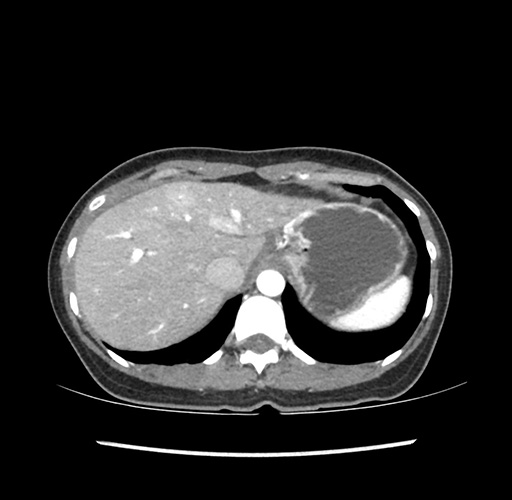

Imaging Analysis

Look through the patient's CT scan to identify any areas of concern for the necessary procedure.

Based on your CT findings, which issue(s) would give reason for "planned slowing down moment(s)" in this case?